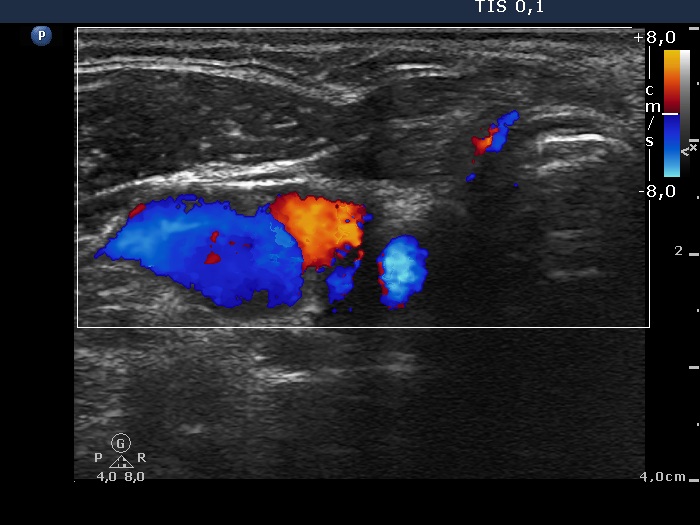

Six years after surgery (first row of images):

Clinical data: A 61-year-old man underwent bilateral thyroid surgery six years ago. According to the final report, total thyroidectomy was performed. Histopathology disclosed benign hyperplastic nodules. Several months before the present examination, the patient noticed a painless mass in the left lobe.

Palpation: a hard, painless mass according to the left lobe.

Laboratory tests: TSH 1.05 mIU/L on daily 87.5 microgram levothyroxine.

Ultrasonography. Muscle fiber and connective tissue was found in the right thyroid bed. Hypoechoic mass was found according to the palpable mass in the left lobe. It had a more hypoechoic discrete lesion with echogenic figures. The mass was avascular.

Cytology resulted in granulation around surgical thread.

A surgical consultation was proposed.